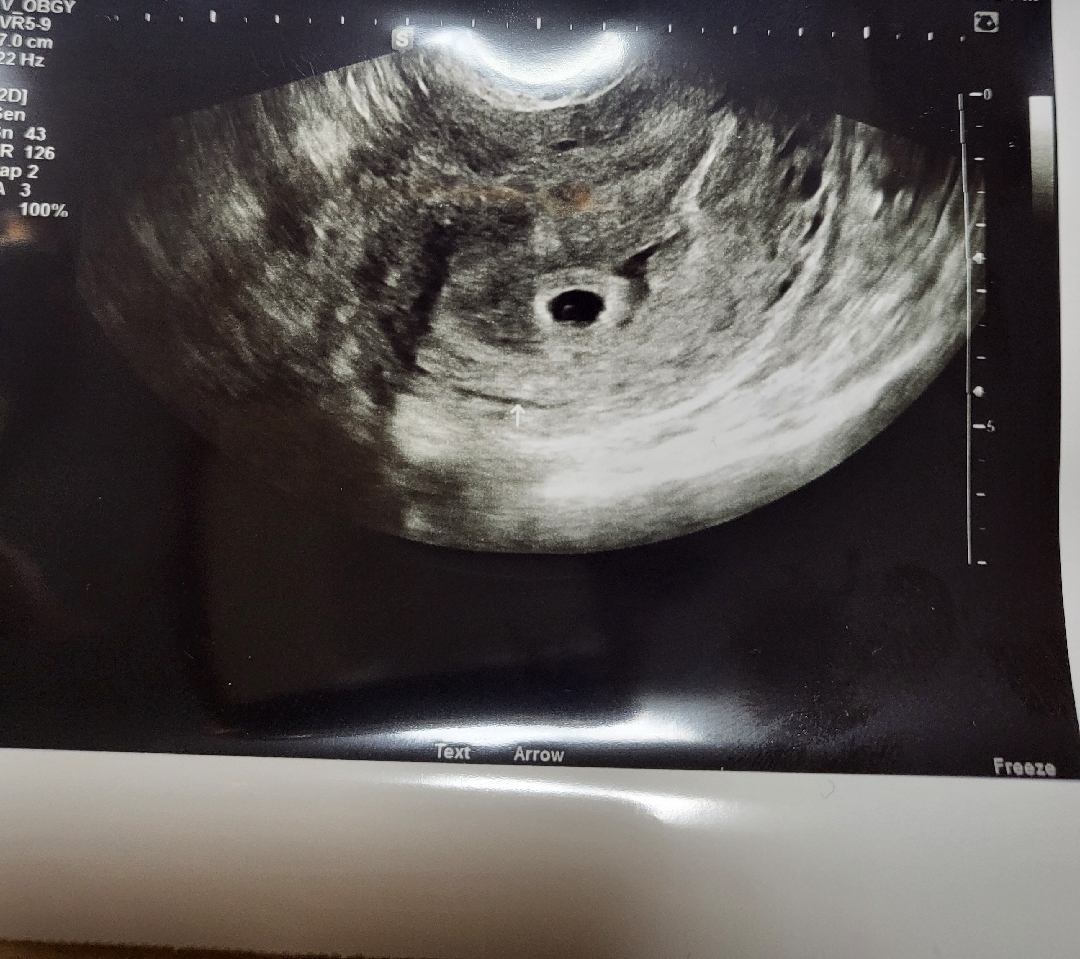

어제초음파로 아기집 확인했어요

행복합니다 건강하게 자라렴❤️